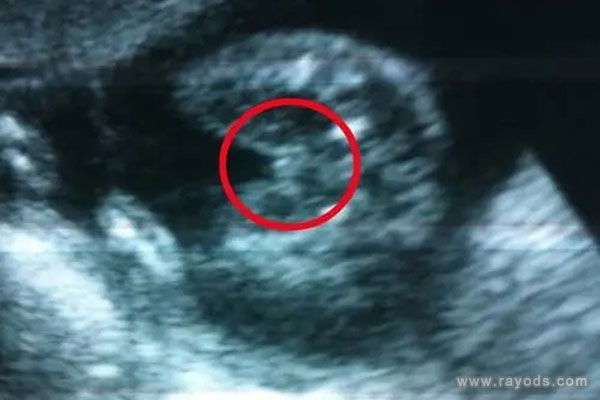

女孩最明显的标志三条白线,b超单子上会有三条白线的明显标志,98%的妈妈都验证过是准的。